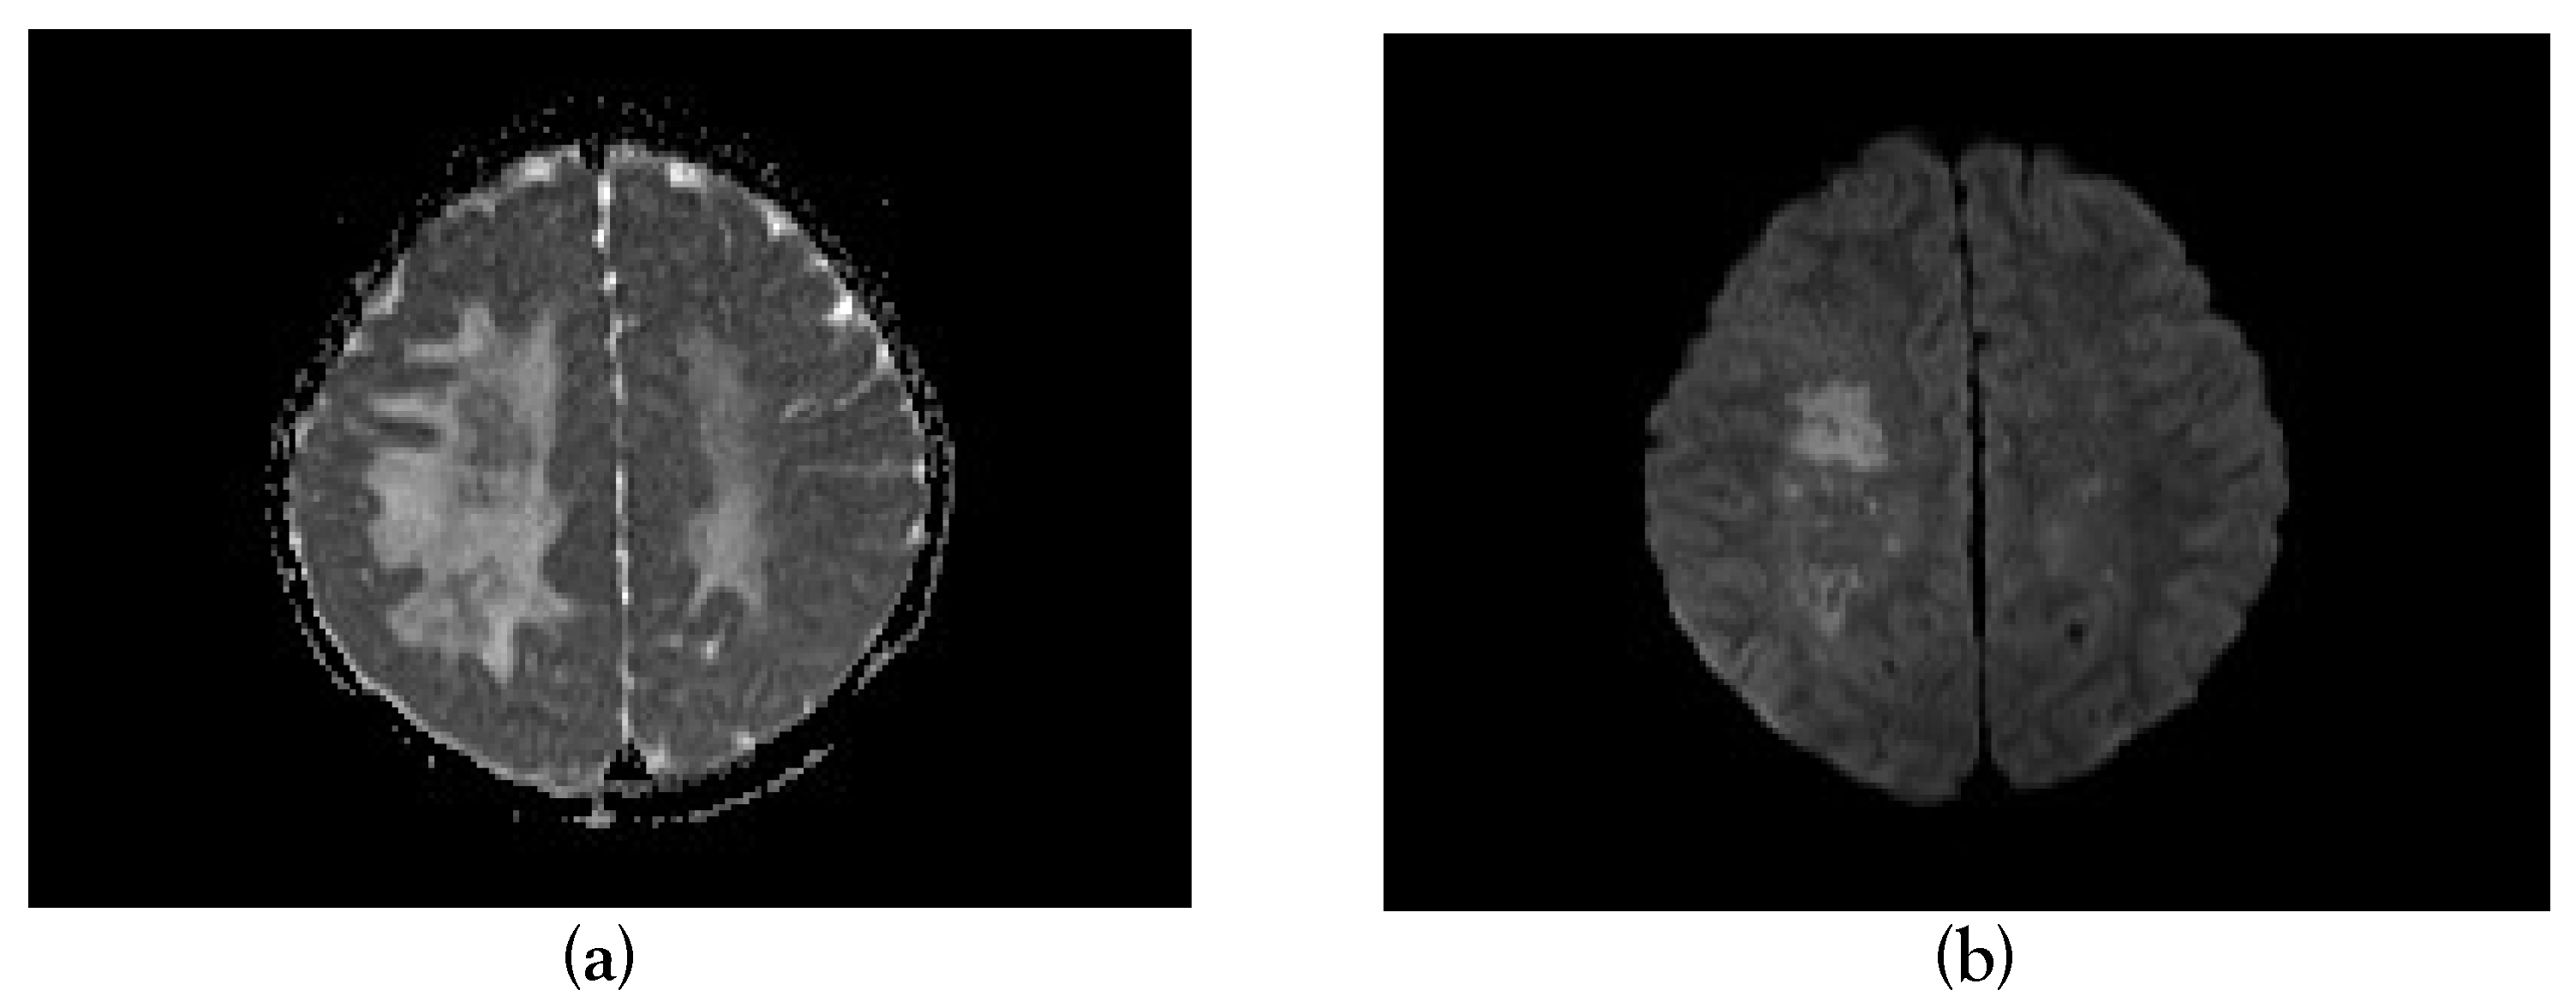

A Case Report of Acute Disseminated Encephalomyelitis Following Severe Dengue in a Child